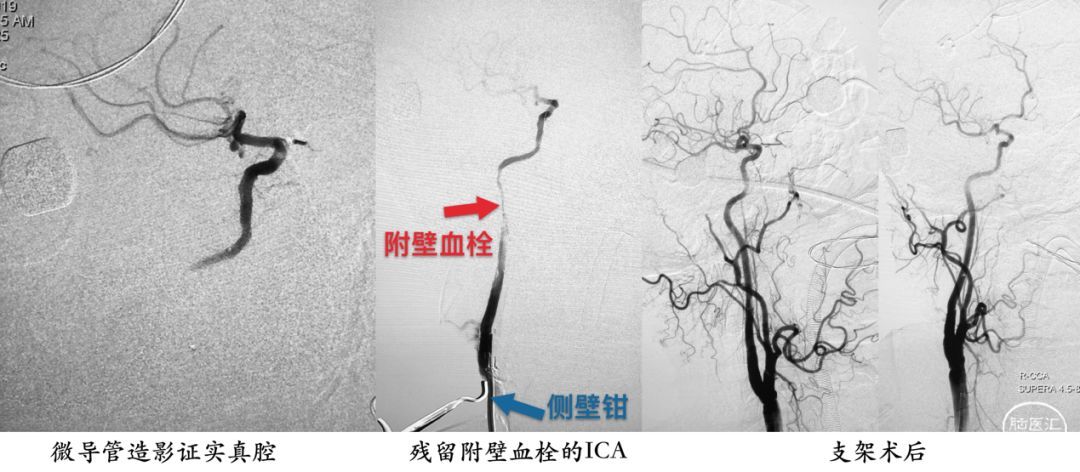

除黑色液体外,剩下的都是由粘稠、脆性较大的慢性血栓充填管腔。直视下,将微导管置入血栓,也就是ICA的管腔,向上走行没有阻力,微导管造影证实真腔后,留置微导丝。

在部分颈动脉缝合后,以侧壁钳夹闭剩余切口,手推造影显示ICA再通,但有明显的附壁血栓,采用网眼可控的Supera支架,完全覆盖血栓处,并在最后放开侧壁钳,以期将残留血栓碎屑冲出体外。